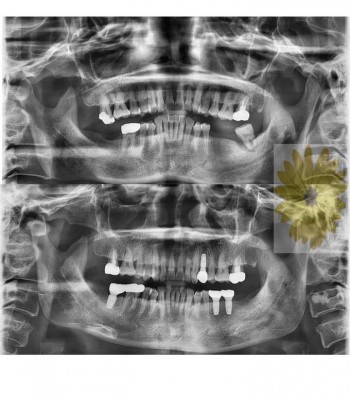

민들레치과 치료 전후사례